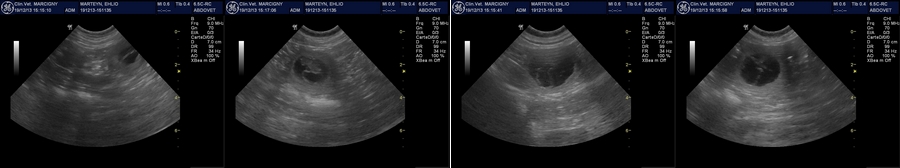

* Ehliodore et Genkini vont nous offrir de beaux bébés, notre jolie miss est gestante !